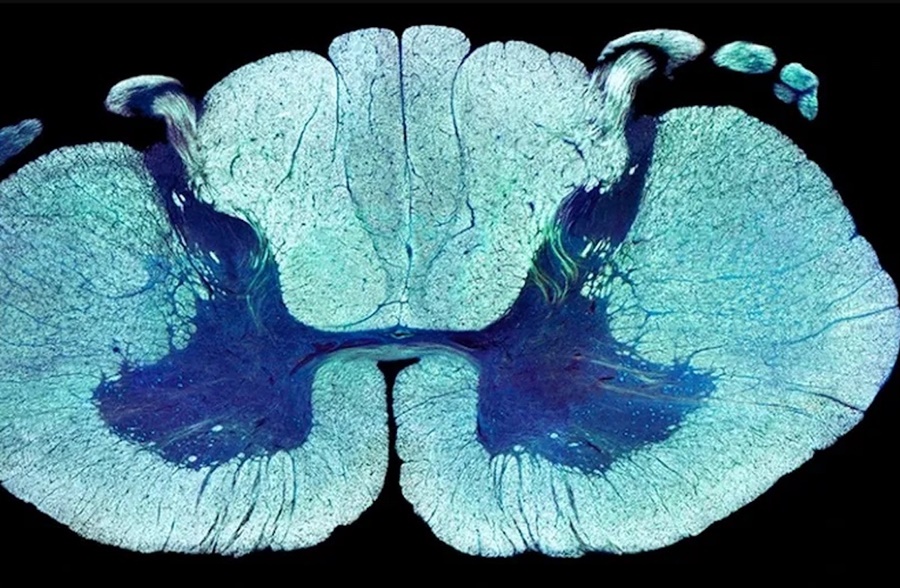

Quatro voluntários continuaram andando mesmo sem os estímulos, segundo resultados divulgados pelo Instituto Federal de Tecnologia da Suíça